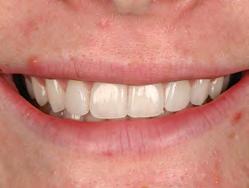

A 31-year-old woman presented with cosmetic concerns regarding her smile and requested a conservative enhancement. After clinical and radiographic analysis, digital 35mm photographs were taken and reviewed by the restorative clinician, technician, and surgeon (Fig 1). A digital impression was taken of the maxillary and mandibular arches using an intraoral scanner (Trios 3, 3Shape; Fig 2), and a smile design was developed with NemoSmile Design 3D software (Nemotec; Fig 3a). This allows for a facially driven smile frame to be created using reference lines of facial and smile proportions and natural teeth shapes and textures from the digital library (Fig 3b).

Fig 1 Preoperative clinical views of a 31-year-old woman presenting with diastemas and limited tooth visibility. (top) Portrait. (center row) Intraoral views. (bottom row) Smile.

4b). This matrix was used to create an intraoral motivational mock-up with bis-acryl composite (Luxatemp Ultra, DMG). This additive mock-up provides the interdisciplinary team with an intraoral translation for evaluation (Fig 5). Upon evaluation of the digital smile frame and the clinical translation, it was determined that multiple esthetic and restorative requirements were necessary for an optimal biologic framework, and the interdisciplinary team determined the best sequence for these procedures. The patient was presented with the interdisciplinary treatment possibilities that included restoring the maxillary anterior teeth and premolars with a minimally

invasive preparationless procedure or with less conservative veneer preparations. The restorative materials discussed included injectable resin composites and ceramic (ie, feldspathic, pressable, machinable). For an optimal biologic framework and health, it was determined that connective tissue grafting would be necessary for treatment of the recessiontype defects on the maxillary left central and lateral incisors, canine, and premolars. The patient opted for the conservative preparationless composite veneers using the injectable resin technique followed by a connective tissue surgical procedure using the tunneling technique.